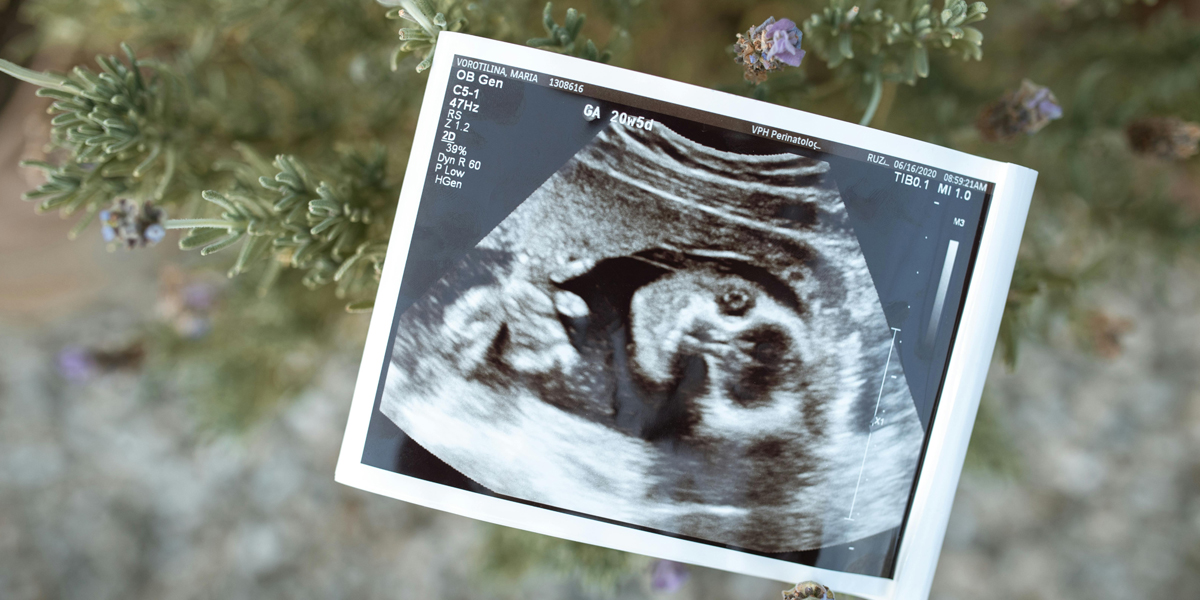

De 20-wekenecho, ook wel de structurele echo genoemd, is het grote onderzoeksmoment. De echoscopist neemt uitgebreid de tijd om alle organen en lichaamsdelen van je baby te checken. Ze kijken naar het hartje, de nieren, maag, blaas, hersenen, ruggengraat en alle ledematen. Ook controleren ze of de placenta goed zit en of er genoeg vruchtwater is.

Bij deze echo kun je vaak ook zien of je een jongetje of meisje krijgt – als je dat wilt weten natuurlijk. En als je baby meewerkt, want soms ligt hij of zij net in een onhandige positie!